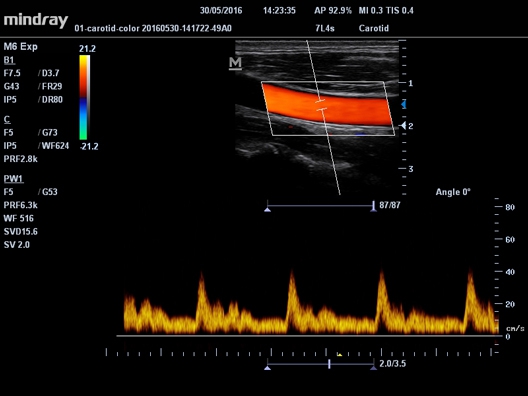

Mindray M-5 - это портативный цветной УЗИ-сканер с широким набором методов сканирования и модулем формирования панорамного изображения. Это устройство объединяет возможности современных стационарных УЗИ-систем и ноутбуков, обладает эргономичным тонким LCD-монитором диагональю 15 дюймов, встроенным аккумуляторным устройством и широким функционалом, что обеспечивает комфортную и эффективную работу.

Mindray M-5 стал популярным среди врачей, благодаря своему небольшому весу, всего 6 кг. Он идеально подходит для использования в скорой помощи и предоставления медицинской помощи на дому. Несмотря на то, что M-5 относится к среднему классу ультразвуковых сканеров, он не уступает конкурентам в своей категории по мощности и интеллектуальным возможностям.

При необходимости сканер может быть установлен на специальную тележку, что делает его стационарным. Это особенно актуально, если у вас есть только один диагностический кабинет, но требуется много мобильных сеансов.

• Автоматический режим расчета комплекса интима-медиа, определяющий толщину и сопоставляющий ее со стандартами